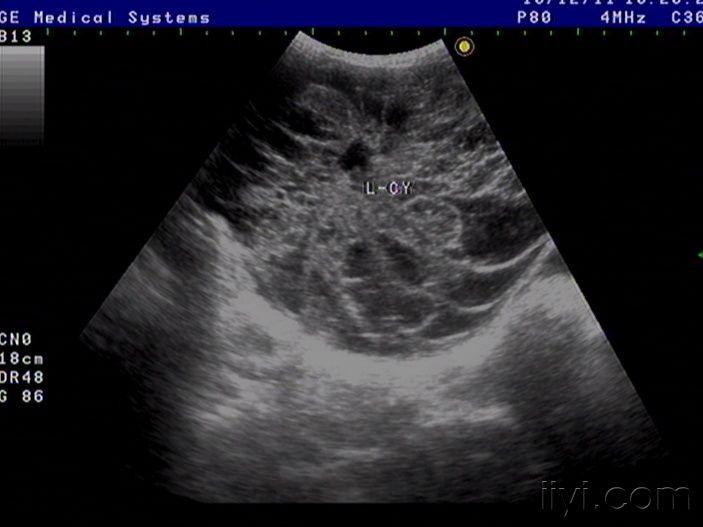

42岁女性患者,自觉腹胀一月余,未诉其它不适,月经规则,彩超中下腹部至盆腔左右各一包块如图,请老师看看像什么,以前没见过这样的这么大的包块

粘液性囊腺癌

是啊,网膜都已经广泛转移了,